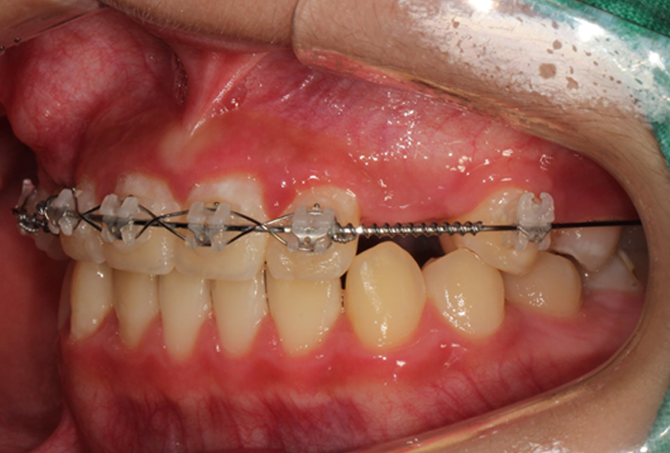

설측교정은 치아 안쪽(설측면)에 초소형 장치로 보이지 않게

아름다운 미소를 만드는 고난이도 프리미엄 교정 치료입니다.

난이도가 높은 만큼 풍부한 진료 경험이 중요합니다.

강남에서 다년간 설측교정에 특화된 경험을 바탕으로,

3D 디지털 기술을 활용한 맞춤 설계, IDBS방식을 통한

정밀하고 불편감 없는 치료를 제공합니다.